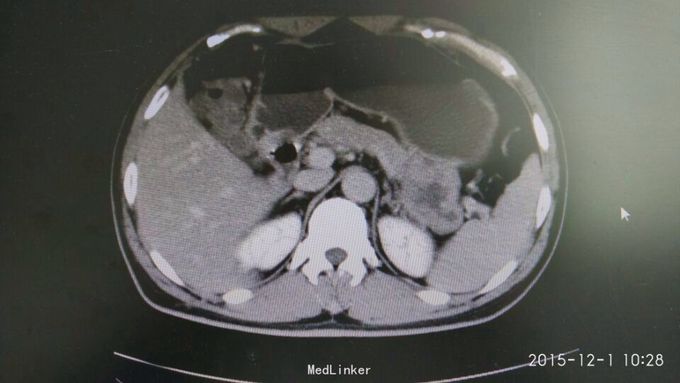

间断性上腹部隐痛,加重两月余。 于15年前左上腹间断隐痛,可忍,伴肩背部放射,活动后缓解,无恶心呕吐,大小便正常,未行特殊处理。2月前,上述症状出现并加重,伴腹泻,伴肩背部放射,无皮肤粘膜黄染。

巩膜无黄染,心肺无异常,腹部平坦,无腹壁静脉曲张,肠鸣音未见异常,左上腹压痛(-),无反跳痛,腹部未触及包块,肝脾肋下未及,Muephy(-),双肾区叩击痛(-),移动性浊音(-)

胃间质瘤 拟行胃间质瘤切除术

瘤体较大,超过5cm,术中注意与胰腺关系,如果压迫胰腺或压迫脾脏血管,是否考虑部分胰腺切除及脾切除,是否考虑胃空肠吻合。